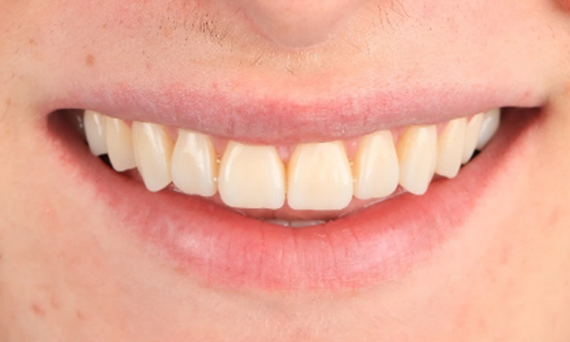

Before: Clinical Situation pre-op. Trauma of upper central incisors

After: Adhesively bonded restorations.

Minimal Preparation Veneers after Trauma of Upper Central Incisors

Restoration with a highly esthetic material in one day after trauma to the maxillary central incisors.